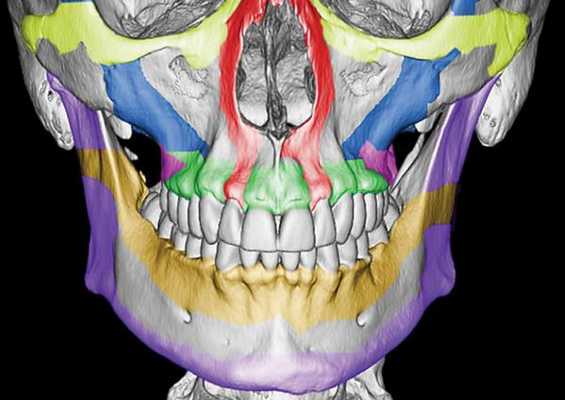

Чтобы понимать, как ломается верхняя челюсть следует сначала остановиться на её анатомии. Верхняя челюсть (лат. maxilla) — парная кость, которая у взрослого человека представляет собой единую систему. Она имеет две больших полости (верхнечелюстные пазухи) и участвует в формировании ещё трёх полостей — глазницы и полости носа. По своему строению это ажурная, тонкая структура, находящаяся в передне-средней части черепа.

Она соединена с другими костями лицевого скелета и основания черепа: скуловой, лобной, носовой, слёзной, решётчатой, клиновидной, нёбной.

Выделяют так называемые отростки верхней челюсти: скуловой отросток (соединяется со скуловой костью и формирует ширину лица ), лобный отросток (формирует плавность профиля спинки носа и опосредованно участвует в формировании очертаний глазниц), нёбный отросток (формирует твёрдое небо, срастается по средней линии нёбного шва с противоположной верхнечелюстной костью) и альвеолярный отросток (содержит в себе зубы).

Верхняя челюсть представляет собой достаточно прочную структуру, благодаря местам особой прочности — контрфорсам, которые представляют собой костные утолщения. Различают лобно-носовой, альвеолярно-скуловой, крыловидно-нёбный и нёбный контрфорсы. Забегая вперёд, стоит сказать, что при оперативном лечении переломов верхней челюсти эти "линии" используются для надёжной, ригидной фиксации (остеосинтеза) повреждённых костей.

Однако в строении верхней челюсти есть и участки сниженной прочности. Они находятся вдоль швов, соединяющих верхнюю челюсть с другими костями лицевого скелета, а также с костями основания черепа.Таким образом, можно понять, что при чрезмерном механическом воздействии верхняя челюсть чаще всего ломается именно в местах перехода от прочных участков к слабым или просто в слабых местах [4] .

По этой причине линия перелома часто проходит не строго по анатомическим границам верхней челюсти, а смещается на соседние, связанные с ней кости. Это объясняет, почему в практике челюстно-лицевых хирургов встречаются не столько переломы самой верхней челюсти, сколько её "выламывание" с фрагментами других костей лица и основания черепа.

Симптоматика переломов костей средней зоны лица многообразна, поэтому для постановки точного диагноза требуется выполнение рентгенологической диагностики. Самым современным и точным методом является компьютерная томография . С её помощью челюстно-лицевой хирург имеет возможность точно определить локализацию линии разъединения костных фрагментов и тип перелома, выбрать наиболее адекватную и малотравматичную тактику лечения [11] .